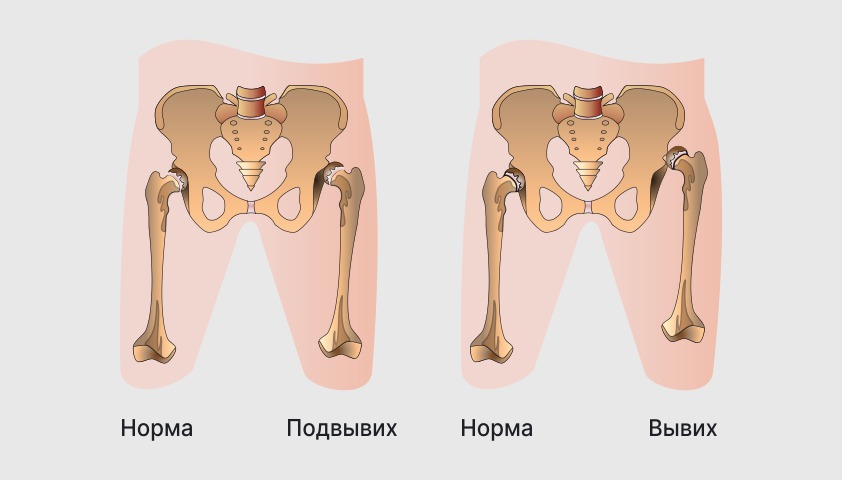

Оссификация тазобедренных суставов: что это и как проявляется?

Раздел: Сокровищница опыта